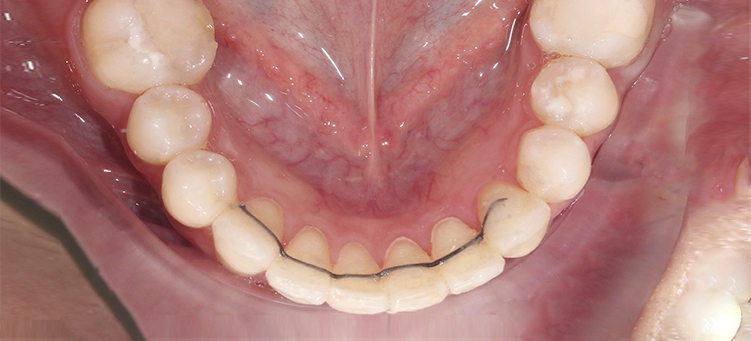

Исправления скученности верхних и нижних резцов